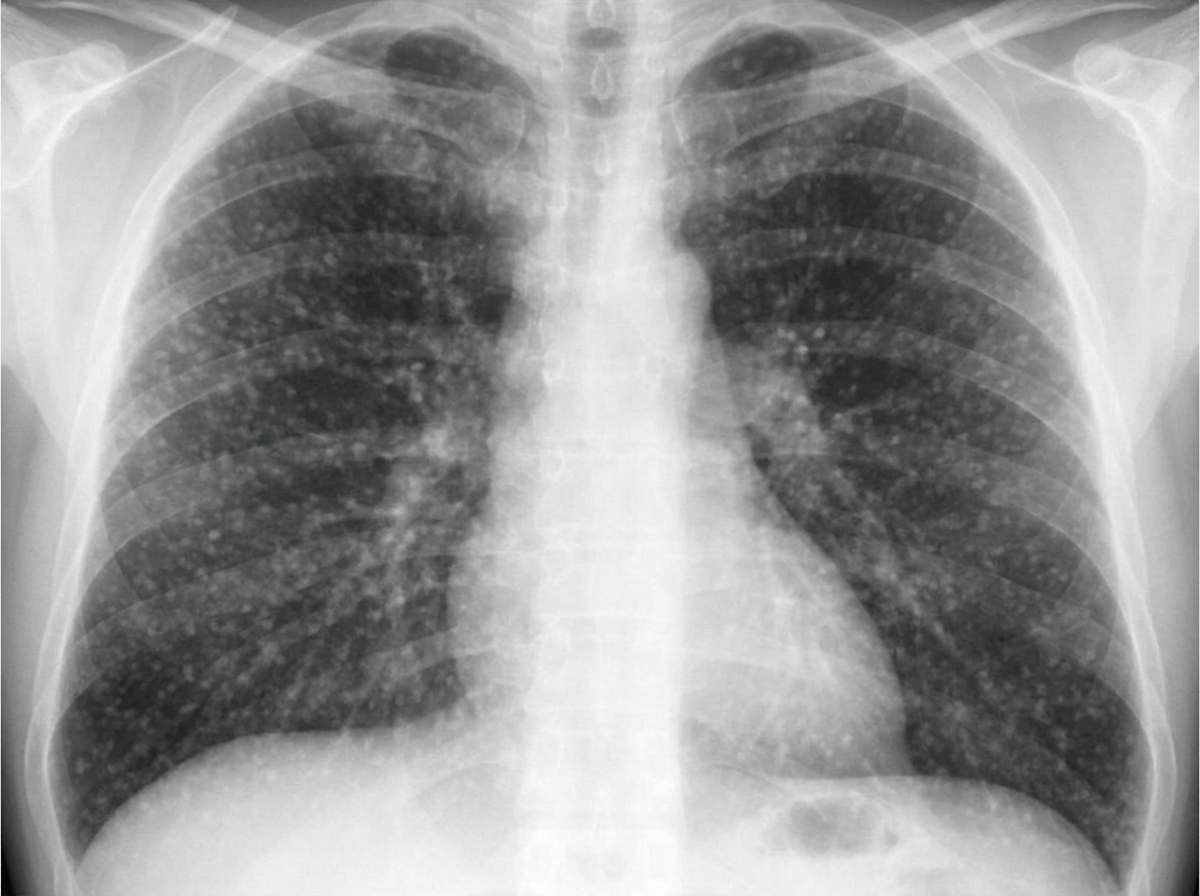

A 68-year-old man presents to the physician with fever, cough, weakness, night sweats, and poor appetite for the past 6 months. Medical records suggest that he has lost 7.5 kg (16.5 lb) of weight during this period. There is no history of breathlessness, nasal discharge, nasal obstruction, palpitations, chest pain, or symptoms related to digestion. He was released from prison 9 months ago after serving a 2-year sentence. His temperature is 38.1°C (100.6°F), pulse is 84/min, respirations are 16/min, and blood pressure is 122/80 mm Hg. Physical examination shows hepatomegaly and generalized lymphadenopathy, and auscultation of the chest reveals diffuse crackles throughout the lung fields bilaterally. On direct ophthalmoscopy, three discrete, yellow-colored, 0.5 mm to 1.0 mm lesions with indistinct borders are seen in the posterior pole. A chest X-ray is shown in the image. Tuberculin skin test with purified protein derivative is negative. What is the most likely diagnosis?